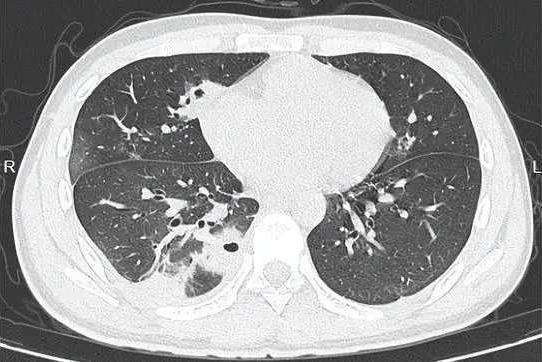

悲剧了!20岁大学生嫌脸上痘痘难看,以为挤掉能快点好,结果,痘痘依旧化脓了,甚至引发高烧,住进了ICU,医生安排CT检查,发现小林肺里有十几个空洞,部分肺组织已经坏死!网友:不知、不知道,一知吓一跳,我都不知道挤了多少个痘痘! 这事儿听着就吓人,谁能想到挤个痘痘能闹到进ICU的地步。小林这情况,医生后来解释说,是因为他挤痘痘的时候,手上的细菌顺着破损的皮肤钻进了血管,一路感染到了肺部,引发了严重的脓毒症。脸上的痘痘看着小,可位置特殊,尤其是鼻子周围那片“危险三角区”,血管直接连着大脑,一旦感染扩散,后果真能要命。 说起来,好多人都有挤痘痘的习惯。对着镜子看到那颗红红的疙瘩,总觉得手痒痒,挤完那一刻还挺有成就感。可很少有人想过,自己的手一天摸这摸那,细菌多着呢,挤的时候稍微没注意,就可能把细菌推进皮肤深层。而且挤痘痘本身就容易把毛囊挤破,让炎症更厉害,本来几天能好的痘,说不定挤完反而肿成大包,留疤都是轻的。 小林这案例算是给所有人提了个醒:脸上的痘痘真不是随便能碰的。尤其是那种又红又肿、摸着还疼的,十有八九是有炎症,这时候挤就是火上浇油。年轻人爱美心切能理解,但比起一时的痛快,还是得讲究方法。长了痘,注意清洁,饮食清淡点,实在严重就去看医生,配点药膏或者口服药,都比自己瞎折腾强。 现在好多人对皮肤问题的认知还停留在“挤挤就好”的层面,觉得医生说的“危险”是小题大做。可真等出事了才明白,身体这台机器精密着呢,一点小伤口处理不好,都可能引发连锁反应。就像小林,本来只是想让脸好看点,结果差点把命搭进去,这教训太深刻了。 各位读者你们怎么看?欢迎在评论区讨论。